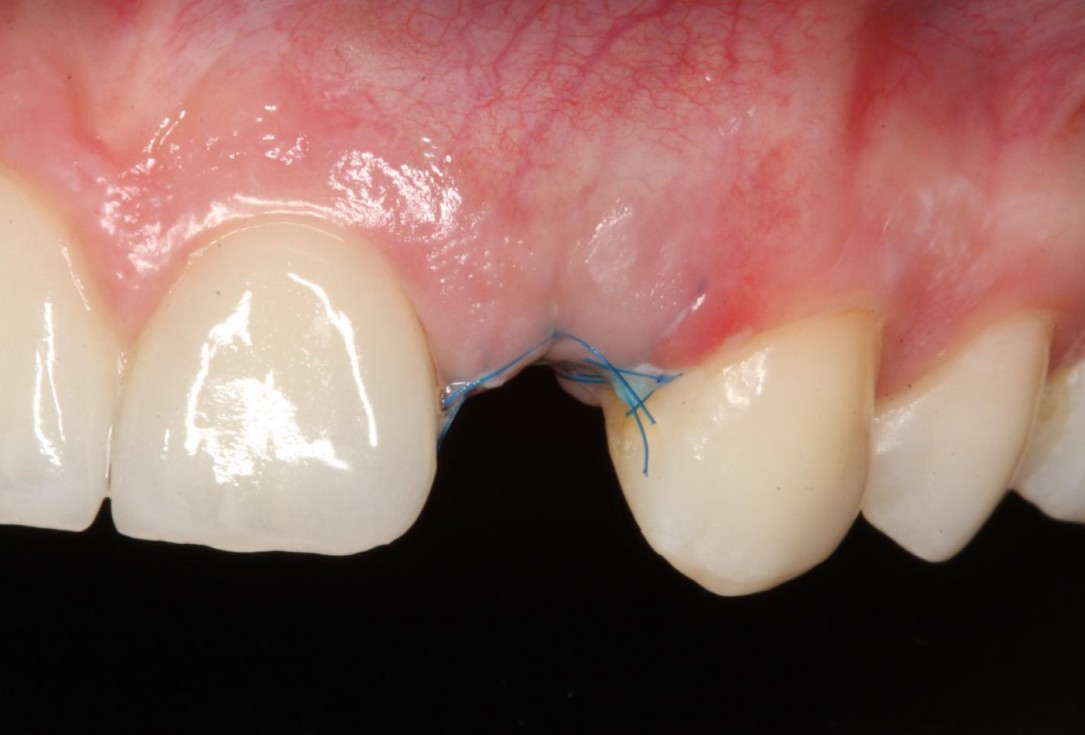

8/12 - Post-operative healing at 2 weeksSoft tissue thickening at immediate implant placement and GBR with mucoderm® and maxgraft® - Dr. A. Puisys